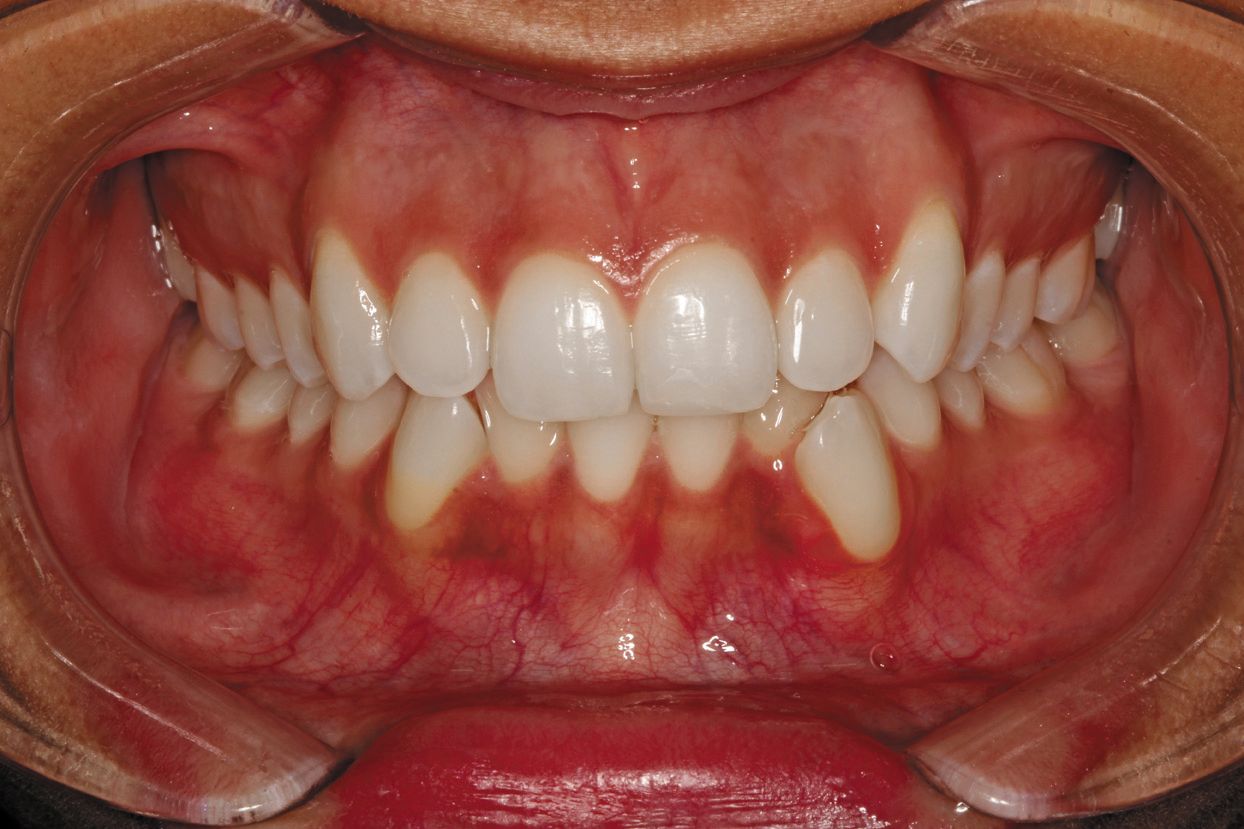

Fig. 7: Retracted biting together photos.

(4) Retracted anterior frontal